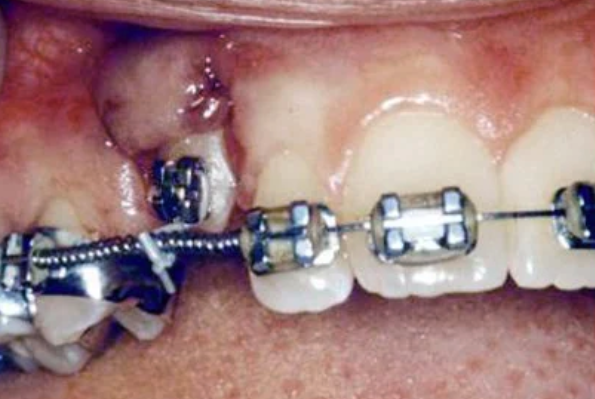

In cases where the eyeteeth will not erupt spontaneously, the orthodontist and oral surgeon will work together to get these teeth to erupt. Each case must be evaluated on an individual basis, but treatment will usually involve a combined effort between the orthodontist and the oral surgeon. The oral surgeon will expose and bracket the impacted eyetooth.

The surgery to expose and bracket an impacted tooth is a very straightforward surgical procedure that is performed in the oral surgeon’s office. For most patients, it is performed using laughing gas and local anesthesia. In selected cases it will be performed under IV sedation if the patient desires to be asleep, but this is generally not necessary for this procedure. If the procedure only requires exposing the tooth with no bracketing, the time required will be shortened by about one half. These issues will be discussed in detail at your preoperative consultation with your doctor.